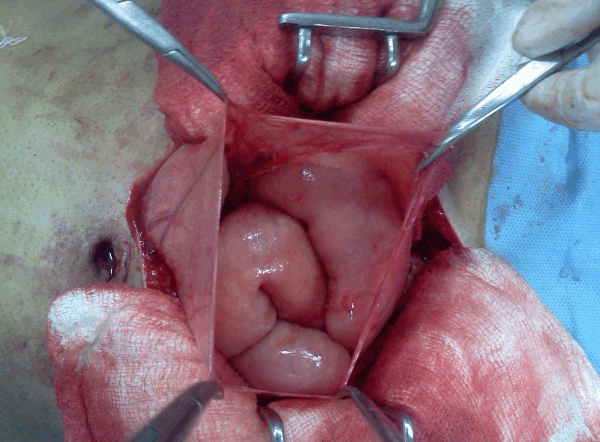

A 28-year-old male presented with generalized abdominal pain, fever and multiple episodes of vomiting. Abdominal pain was episodic and colicky and vomitus was bilious. There was no past history of trauma or surgery. Patient had a past history of three episodes of similar abdominal pain and vomiting three months back. Second episode occurred 12 days after the first episode and third episode occurred 21 days after first episode. Patient was diagnosed as a case of recurrent sub-acute intestinal obstruction by small gut stricture which was confirmed on the barium study at that time. During and after each episode the patient was managed conservatively without any surgical intervention. General physical examination during current episode showed dehydrated appearence, pulse 96/min, blood pressure 110/70 mmHg, and temperature of 99oC. Systemic examination was normal. Abdominal examination revealed distended abdomen, diffuse tenderness and a high pitch bowel sounds. Laboratory parameters were normal. X-ray of abdomen showed multiple air fluid levels. Computed tomography scan of the abdomen revealed conglomeration of gut in a thin sac suggestive of peritoneal encapsulation on the right side. There was displacement of inferior mesenteric vein and the entrapped bowel in left upper abdomen (left paraduodenal hernia). (Figure 1A–B) Gut loops were dilated and had thick walls. Exploratory laparotomy revealed encasement of bowel loops in membrane, typical of peritoneal encapsulation with inter-loop adhesions present in the bowel outside the peritoneal sac. (Figure 2) Gut inside peritoneal encapsulation was dilated, which was suggestive of obstruction. Malrotations of small gut loops was seen. After careful dissection of the membrane, adhesiolysis and release of omental adhesions, a vessel lying on ileal loops, outside the retroperitoneum, was seen which was identified as inferior mesenteric vein (IMV). (Figure 3A-B) The bowel proximal to the abnormally placed IMV was dilated with thickened wall which was suggestive of obstruction. This abnormally lying IMV was constrained by adhesions to small bowel. Peritoneal encapsulation and retroperitonealization of IMV were leading to sub-acute intestinal obstruction. Further exploration revealed a loop of intestine impacted in a left paraduodenal fossa. Diagnosis of the left paraduodenal hernia was confirmed. (Figure 4A-B) Incarcerated segment of bowel in left paraduodenal fossa had signs of strangulation with thickened walls leading to acute abdomen. Resection of incarcerated segment and the closure of hernial orifice was done. Retroperitonealization of anteriorly placed IMV was achieved. Postoperative period was uneventful and patient was discharged after one week. Patient is well on follow up for last 13 months.

Figure 2: Bowel encased in a membrane suggestive of peritoneal encapsulation.